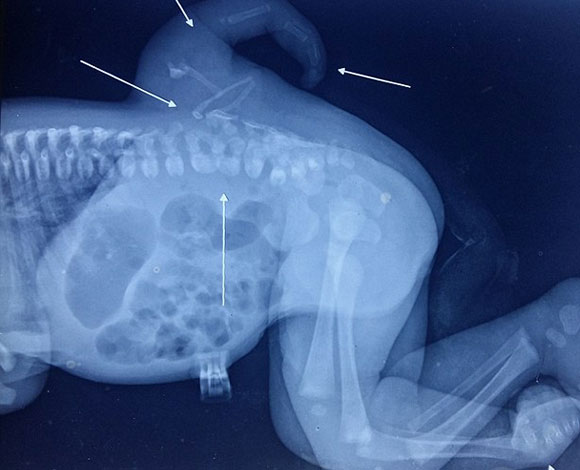

تمكن أطباء من مستشفى غوفيند بالابه بانت في الهند من إزالة ساق ثالثة ولدت بها طفلة ( في ظهرها ) نهاية الشهر الماضي. وكانت تلك الطفلة وتدعى فارشا سينا وتبلغ من العمر الآن عامين ولدت بتلك الساق الاضافية إلى جانب ساقيها الأصليين.

وهي الحالة النادرة التي تصيب طفلا واحدا من بين كل مليون طفل، وهي الحالة المرضية التي تعرف بـ كثرة الأطراف، التي يولد بموجبها الأطفال بأطراف إضافية.

ونقلت بهذا الخصوص صحيفة الدايلي ميل البريطانية عن دكتور دالجيت سينغ، الطبيب الجراح الذي أجرى العملية الناجحة للطفلة فارشا، قوله : كانت تعاني الطفلة من مشكلة كثرة الأطراف، وهي المشكلة التي يولد بها الشخص بأكثر من 4 أطراف. ولم يسبق لنا أن شاهدنا حالة كهذه في الخمسين عاماً الماضية. وتلك هي أول حالة خاصة بكثرة الأطراف ينمو فيها من الحبل الشوكي طرف إضافي بهذا الشكل.

ومن الجدير ذكره أن فارشا ولدت في بارا هيندو راو في مدينة دلهي عام 2014 ثم أرسلت في وقت لاحق إلى مستشفى غوفيند بالابه بانت بهدف إزالة تلك الساق الاضافية جراحيا.